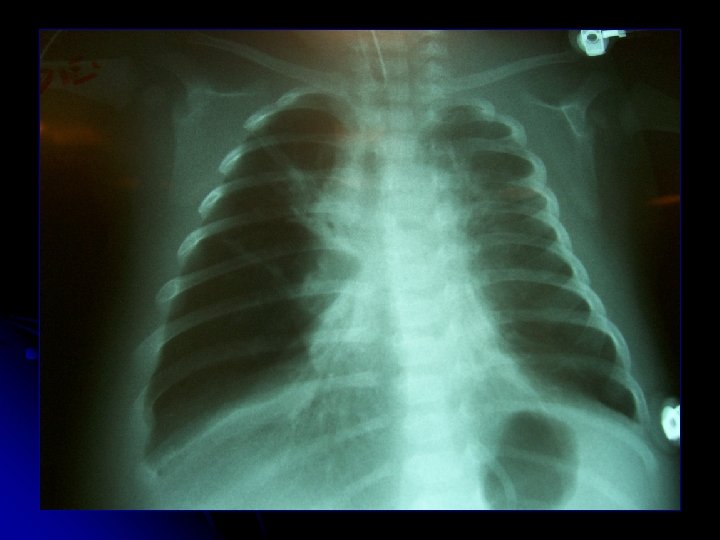

l l ♀ B. C. N. 1 mes 25 días Antecedentes l l Hospitalización reciente x BN + Apneas IFIs (-) Cuadro ingreso l l 1 día tos, coriza, dificultad respiratoria y fiebre Hospitalización 05/08 Sala IRA IFI (+) VRS l Vómitos y diarrea. l Taquicardia y mala perfusión 60 cc/Kg volumen + dobutamina + TET l 07/08: Traslado a UCIP para manejo l

l Ingreso 07/08 l l Sepsis foco pulmonar: cefotaxima 09 - 10/08 l Signología obstructiva severa l l Deterioro radiológico y gasométrico: l l l IO 8 - 13 -16 Rx con atelectasias bilaterales Prono VAFO: PMVA 22 ΔP 43 FR 8 Hz FIO 2 70% 0: 20 hrs: p. H 7, 51 Pa. O 2 59 Pa. CO 2 39 Pa/FIO 2 84 IO 25, 9 l l Corticoides, 2, ipatropio, Mg, Ketamina, AMF